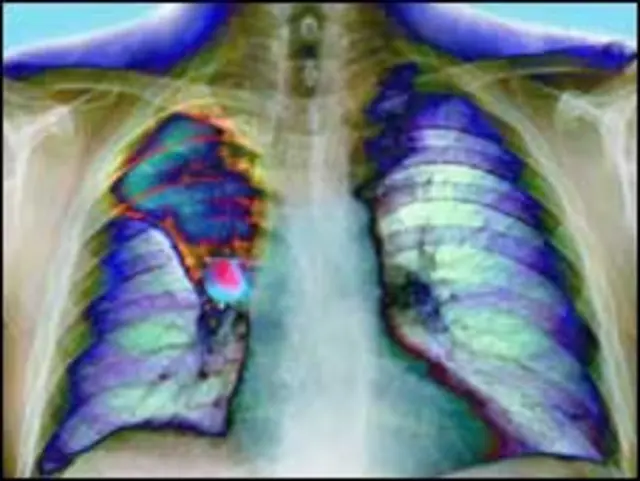

फेफड़ों के कैंसर की पहचान का नया तरीका

फेफड़े का कैंसर मुख्य रूप से धूम्रपान की वजह से होता है और दुनिया भर में ये सबसे जानलेवा कैंसर है.